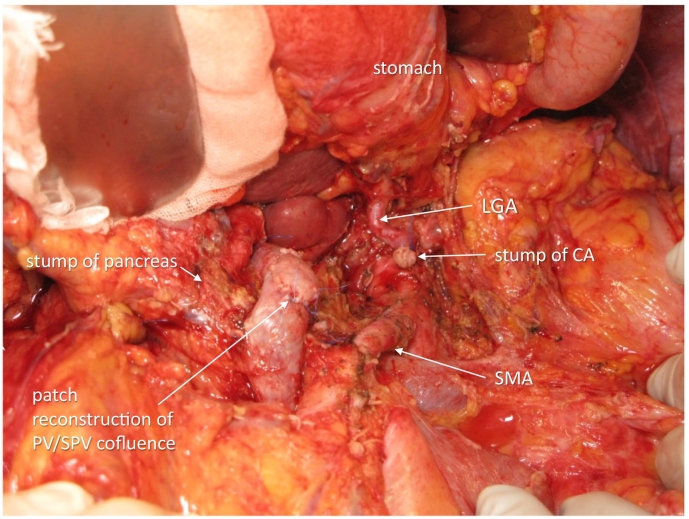

The operation was done 309 days after the first hospital visit and 29 days after the last administration of chemotherapy. The abdomen was entered via upper to middle midline skin incision. No liver and peritoneal metastases were observed. The absence of cancer cells in the nerve plexus was confirmed at (1) the origin of the proper hepatic artery and gastroduodenal artery and (2) the origin of the left gastric artery. The pancreas was cut along the right border of the PV, and there were no cancer cells with patchy deciduation of exocrine tissues and fibrous tissue proliferation at the cut surface; thus, DP-CAR, preserving the left gastric artery, was selected asss a preferable procedure ref. [8], ref. [9], ref. [10]. The CA was severed just distal to the origin of the left gastric artery. The nerve plexus around the SMA was circumferentially dissected 4 cm from its origin. The confluence of the splenic vein to the SMV/PV was widely resected and reconstructed with the right iliac vein patch (Fig. 4). The operative time was 646 min, and blood loss was 873 g. Postoperatively, the patient suffered from slight anorexia but with no pancreatic fistula and was discharged on postoperative day 25.